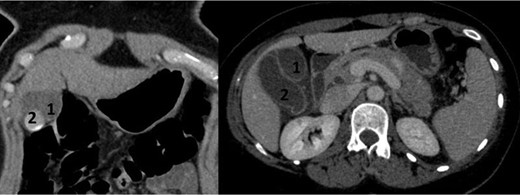

A 39-year-old healthy female, presented to our emergency department due to abdominal pain, nausea and vomiting. She was febrile, with a tender right hypochondrial and epigastric region. Her laboratory results showed a normal complete blood count and C-reactive protein level. Liver function test showed an elevation in total bilirubin at: 42 mmol/L, direct bilirubin level at: 29 mmol/L, gamma-glutamyl transferase (GGT) level at :160 U/L and Lipase level at: 34 000 U/L. An abdominal US showed two separate gallbladders with a sludge (Fig. 1). Abdominal CT scan showed a Balthazar grade C pancreatitis and confirmed the presence of a double gallbladder (Fig. 2). An MRCP confirmed the double gallbladder (Fig. 3). An ERCP was performed with evacuation of biliary debris in the common bile duct (CBD). The patient was discharged home after appropriate medical treatment a couple of days later with a full normal liver function test. Two months later, a laparoscopic cholecystectomy was performed where the two gallbladders were dissected with a dome-down technique, from the gallbladder fundus towards the neck (Fig. 4), the cystic duct and artery were identified. An intraoperative cholangiography was performed which showed patent intrahepatic ducts, cystic and CBD (Fig. 5). A Hem-o-lock® clip (WECK Closure System; Teleflex Inc., Morrisville, NC, USA) was then placed on the main cystic duct (Fig. 6), and another Hem-o-lock® clip was placed on the cystic artery. Figure 7 showing the gross specimen. The final histopathology report concluded two separate gallbladders, each having its own cystic duct, with both cystic ducts joining to form a main cystic duct.

CT scan in frontal and axial slices showing two distinct gallbladders (1 and 2) with cholelithiasus in one of them.